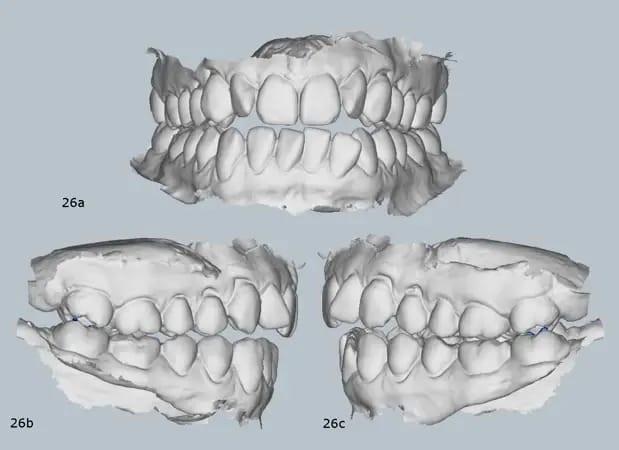

Клинический осмотр выявил передний открытый прикус, по классификации III класса, сужение верхней челюсти, легкая скученность в обеих челюстных дугах и отклонение средней линии нижней челюсти вправо. Верхняя челюсть имела треугольную форму, в то время как нижняя челюсть была квадратной по форме (фото 2).